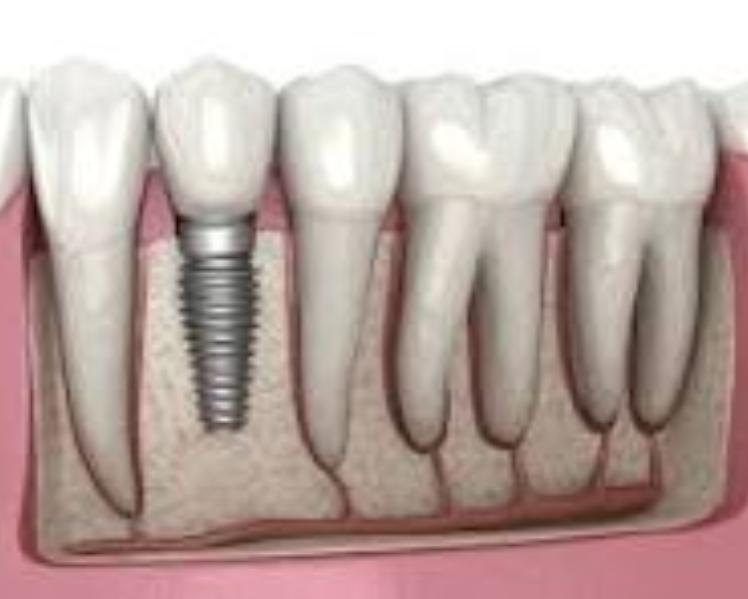

Implant

I came here for a tooth implant and extraction, and it was an excellent experience. Dr. Ruchi is very supportive and an ...